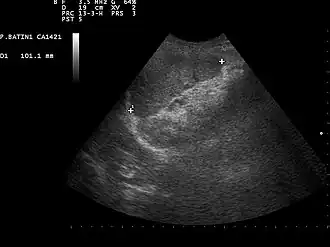

Ultrasound image of a normal spleen that may be seen in part of the eFAST

2. Left upper quadrant of the abdomen (perisplenic view). Left upper quadrant is examined by working your probe down the midaxillary line starting at the left 8th rib to the 11th rib. This examines for free fluid around the kidney and spleen.